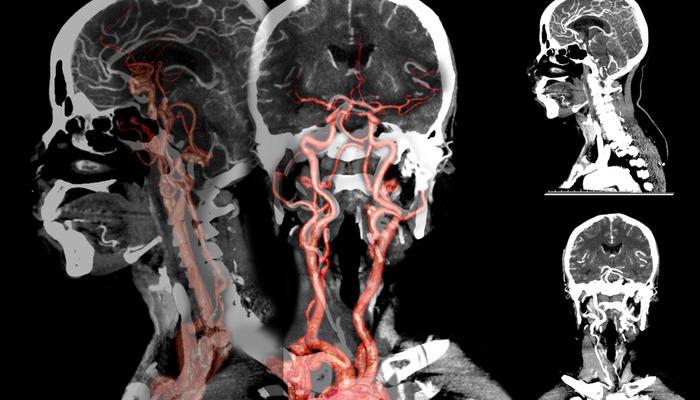

Doç. Dr., beyin kanamasının erkeklerde kadınlara göre daha sık görüldüğünü söyledi. Dr. Çakın, şunları söyledi: “Anevrizmal kanamalar, beyin atardamarlarındaki kabarcıklar nedeniyle meydana gelen beyin kanamaları olarak biliniyor. Özellikle sonbahar ve ilkbahar başlarında bu kanamaların yüzde 10 oranında arttığı gözlendi. Sigaranın etkisiyle beyindeki damarlar tıkanıyor.”

Doç. Dr., beyin kanamasında genetik hastalıkların etkili olabileceğini söyledi. Hakan Çakın, “Yüksek tansiyon, sigara kullanımı ve ileri yaşa bağlı olarak oluşan bu kabarcıklar, mevsimsel döngülerde daha çabuk ortaya çıkıp beyin kanamalarına neden oluyor. Genetik anevrizmalara da daha sık rastlanıyor. Çocukluk döneminde, özellikle Japonya ve Finlandiya’da, ancak “ülkemizde bu kadar yaygın değil. Belli bir yaştan sonra özellikle 30-50 yaş sonrasında hipertansiyon ve sigara kullanımının bu soruna etkisi büyüktür. At nalı böbrek hastalığı, diyaliz hastalarında ya da tansiyon sorunları ve genetik bozukluklar genç yaşta görülen bireylerde etkili olabiliyor” dedi.